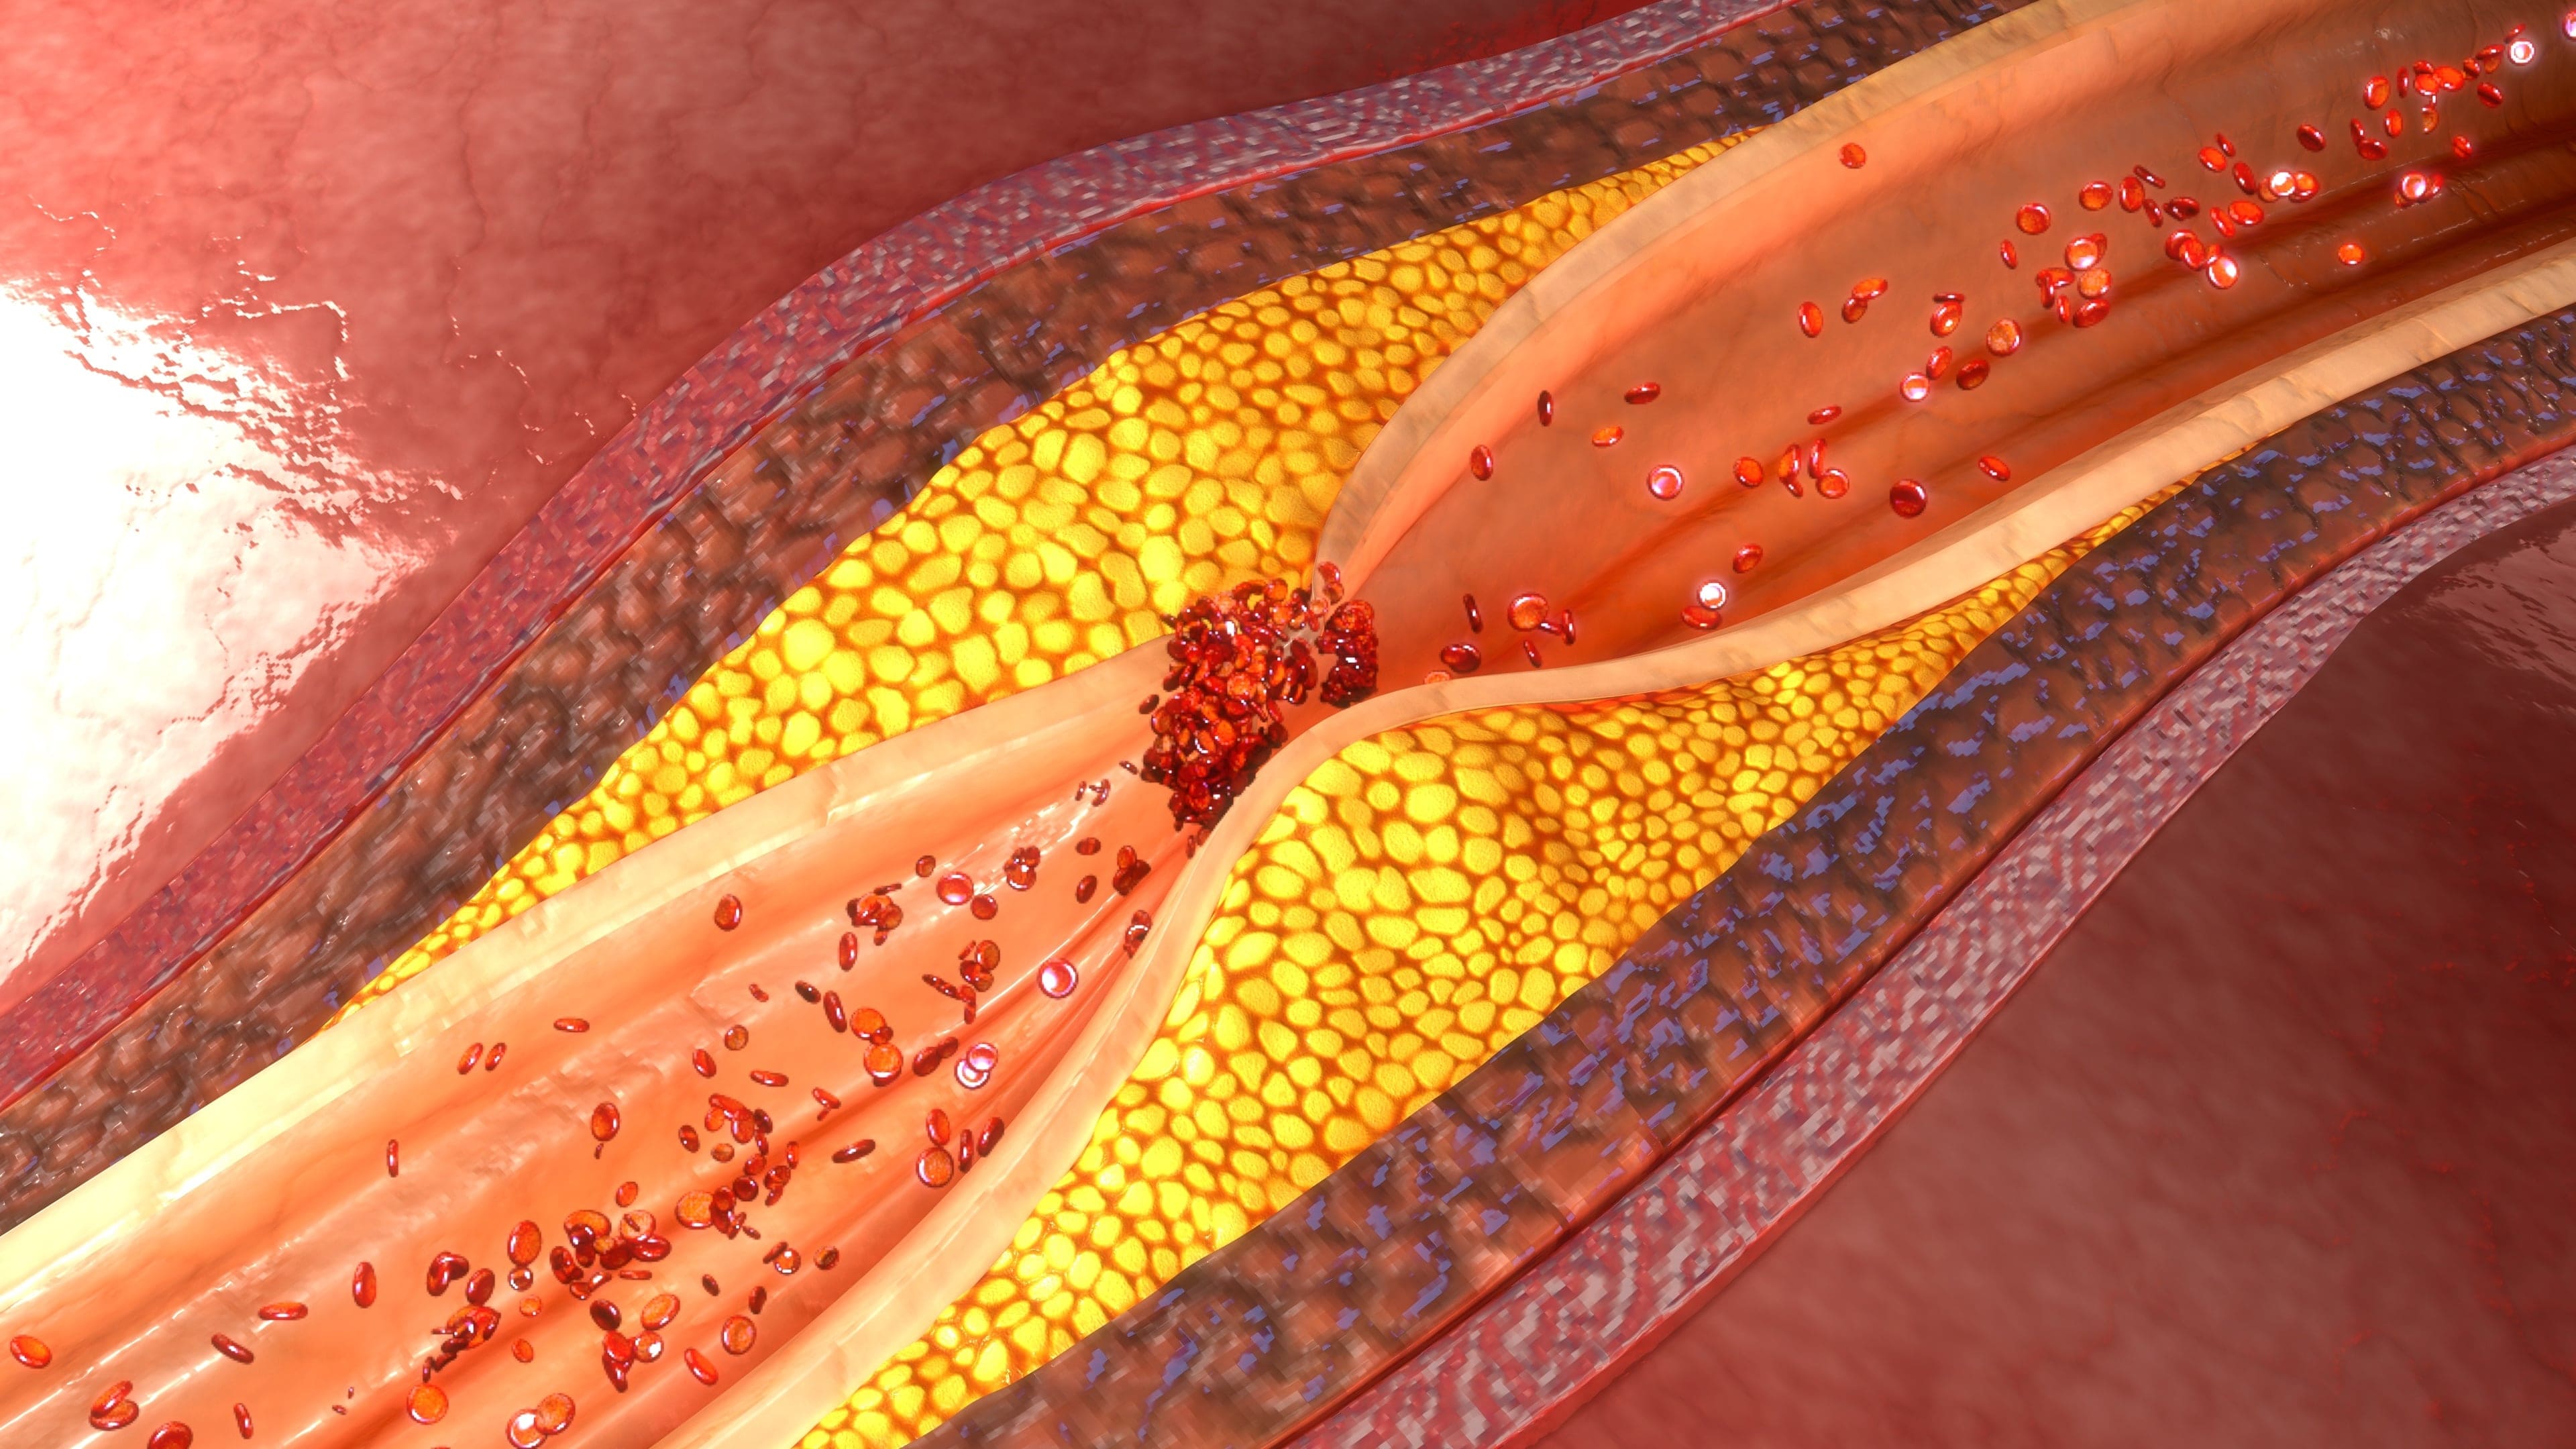

Coronary artery disease (CAD) is taking more complex form than the previous era and it requires special skill-set to manage it.